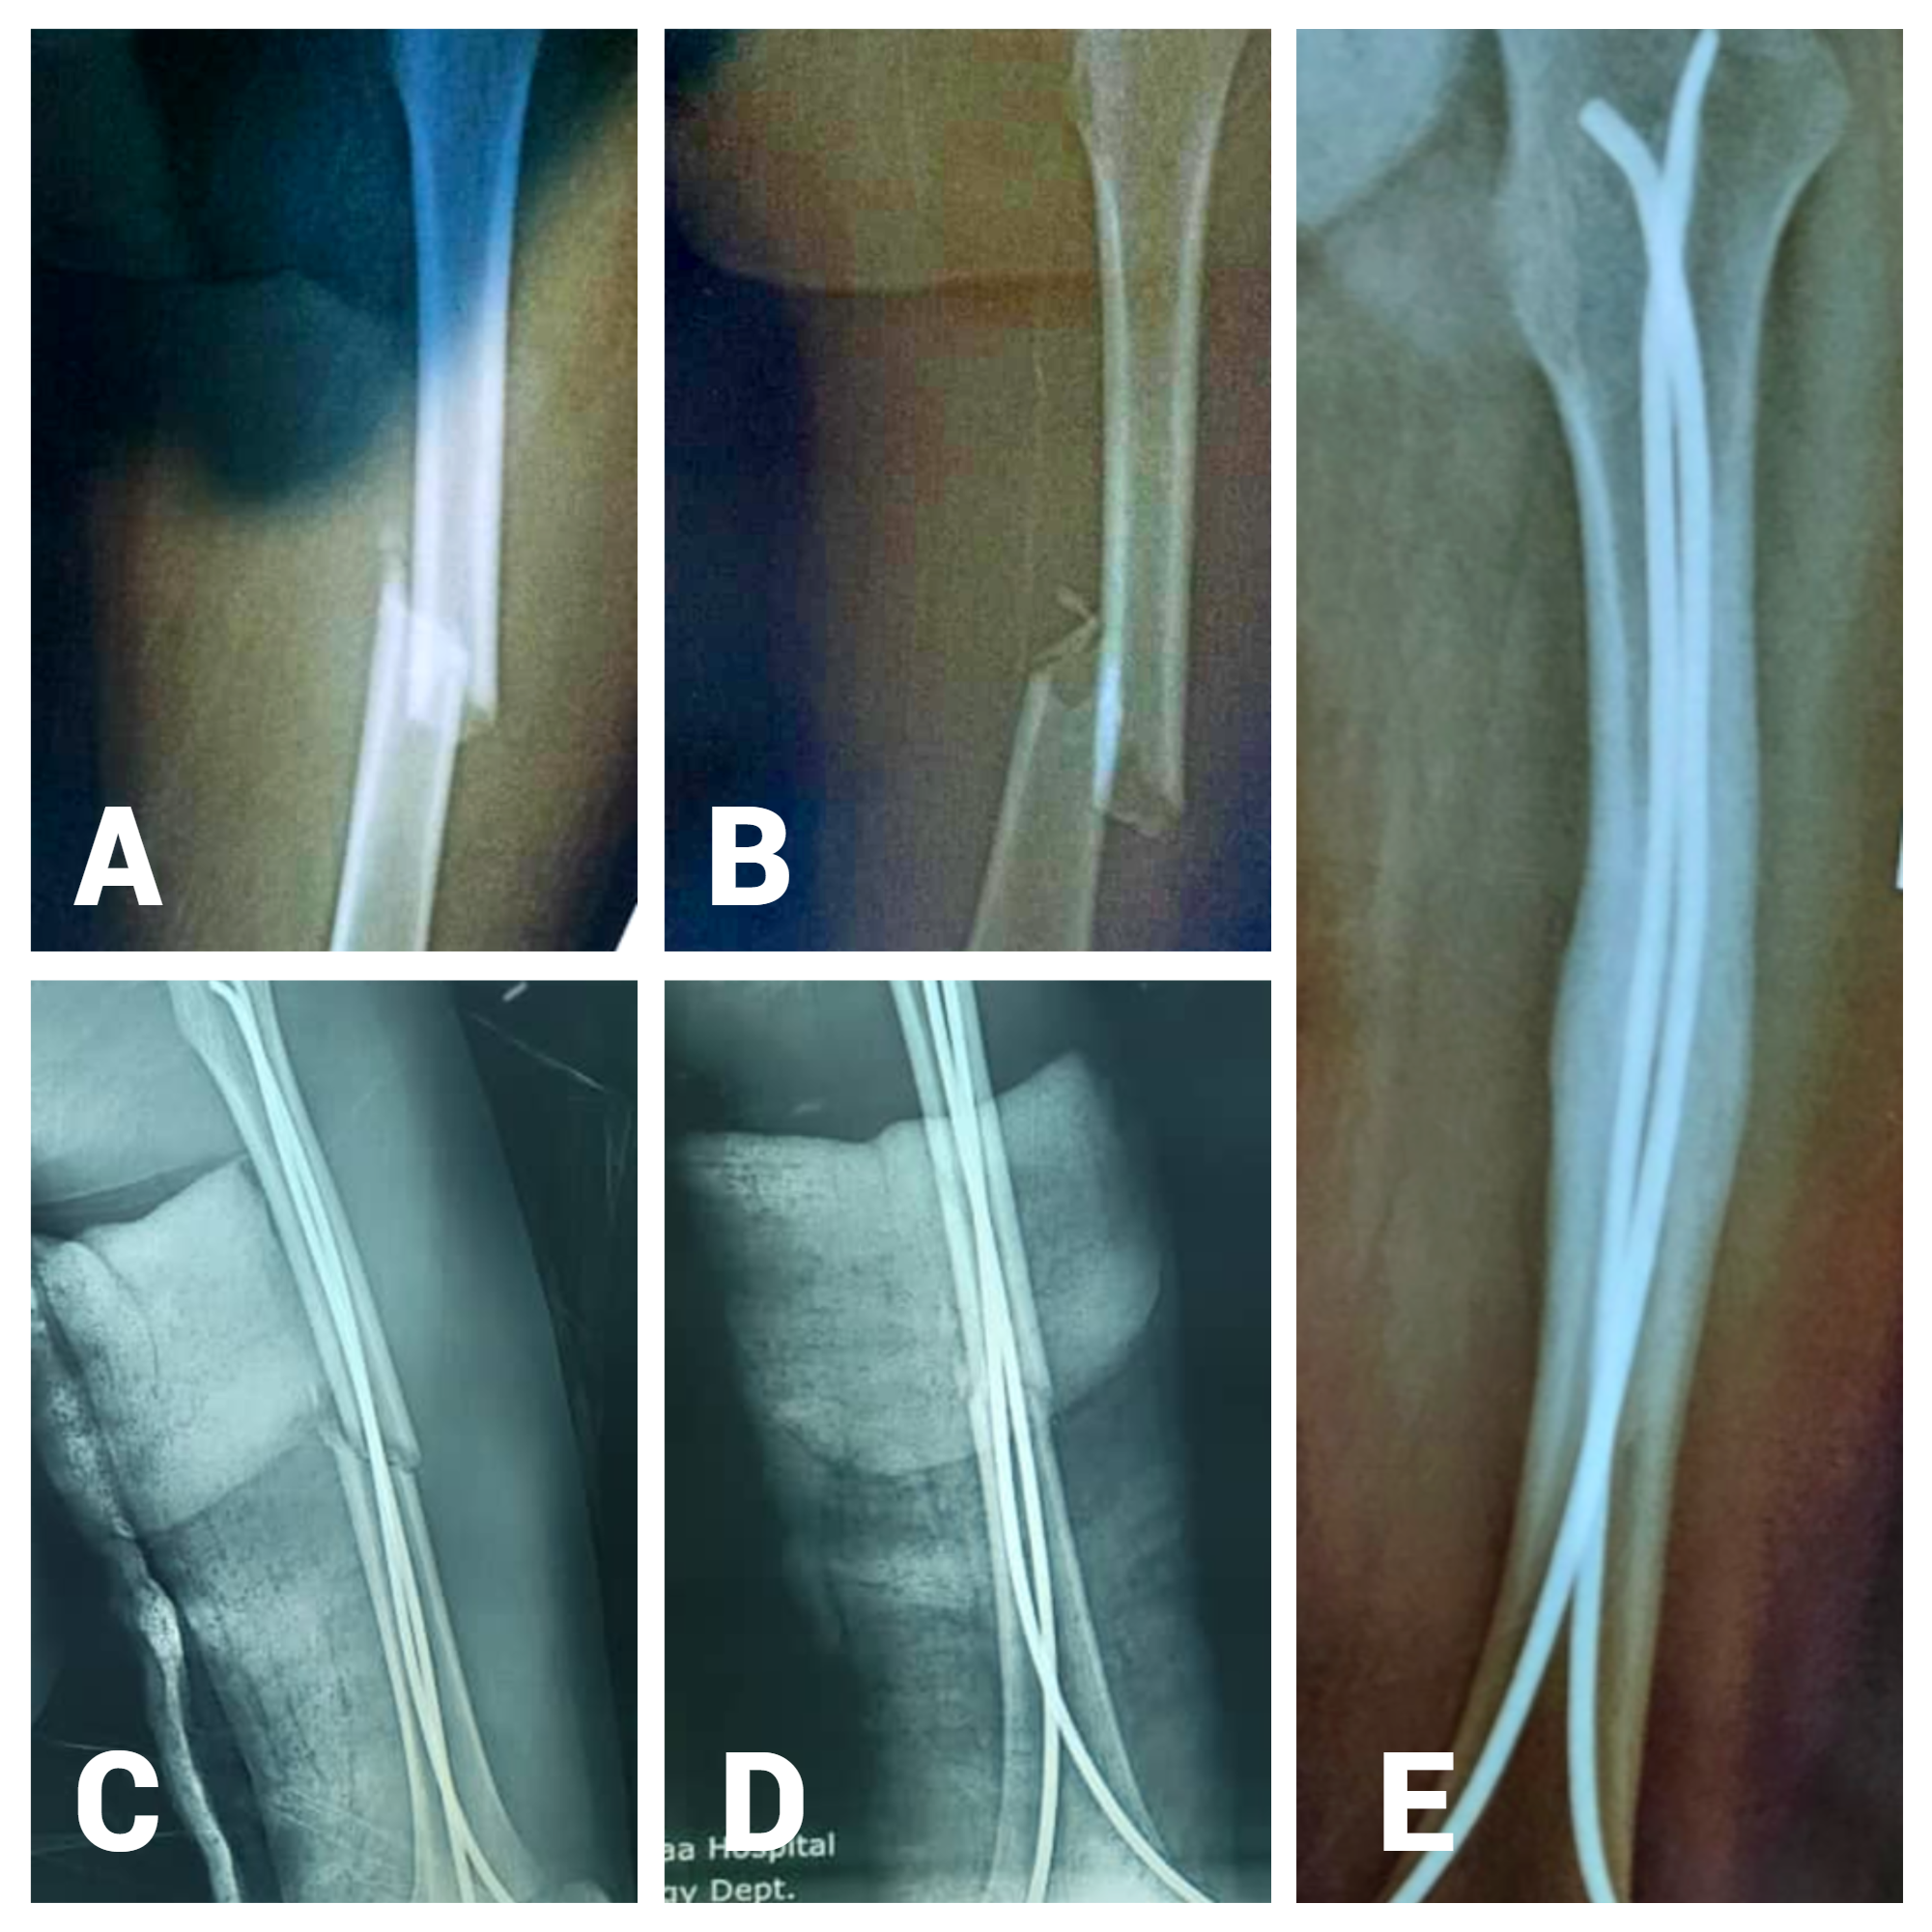

Functional Outcome of Femoral Fracture in Children Treated with Titanium Elastic Nailing System (TENS): A Prospective Study in Sana'a, Yemen

Introduction: This study aimed to evaluate the functional outcomes of pediatric femoral shaft fractures treated with a Titanium Elastic Nailing System (TENS) in two tertiary hospitals in Sana'a, Yemen, between 2021 and 2023. The primary objective of this study was to assess the efficacy and safety of TENS for achieving bone union, restoring limb function, and minimizing complications in a resource-limited setting.

Materials and methods: This prospective observational study was conducted at Al-Thawra Modern General Hospital and Al-Kuwait University Hospital, Sana'a, Yemen. Twenty children aged six–13 years with closed unilateral femoral shaft fractures were treated using TENS. Functional outcomes were assessed using Flynn's criteria, which evaluates alignment, leg length discrepancy, and perioperative complications. Follow-up visits were conducted four, eight, 12, and six months postoperatively.

Results: The mean age of the participants was 9.06 ± 1.9 years, with 14 males (70%) and six females (30%). Road traffic accidents were the most common cause of injury (10 cases, 50%). Excellent functional outcomes were observed in 15 cases (75%), and satisfactory outcomes in five cases (25%). Complications were minimal, with pain at the nail insertion site reported in three patients (15%), limb length discrepancy in one patient (5%), and malalignment in one patient (5%). No major complications such as nonunion or infection were observed.